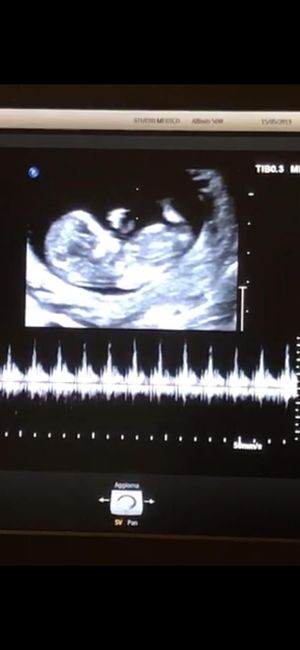

Buongiorno!! Chi è brava a spiegarmi il metodo Ramzi e sa azzeccarci? 😊

Mancano ancora tantissime settimane alla morfologica, che avrò il 15 Luglio, mi ritrovo spesso a fantasticare se sarà Filippo o Lucrezia, io mi sento maschio ma non si sa mai. Mi affido a voi esperte di Nub Theory, cosa dite maschio o femmina?? ...